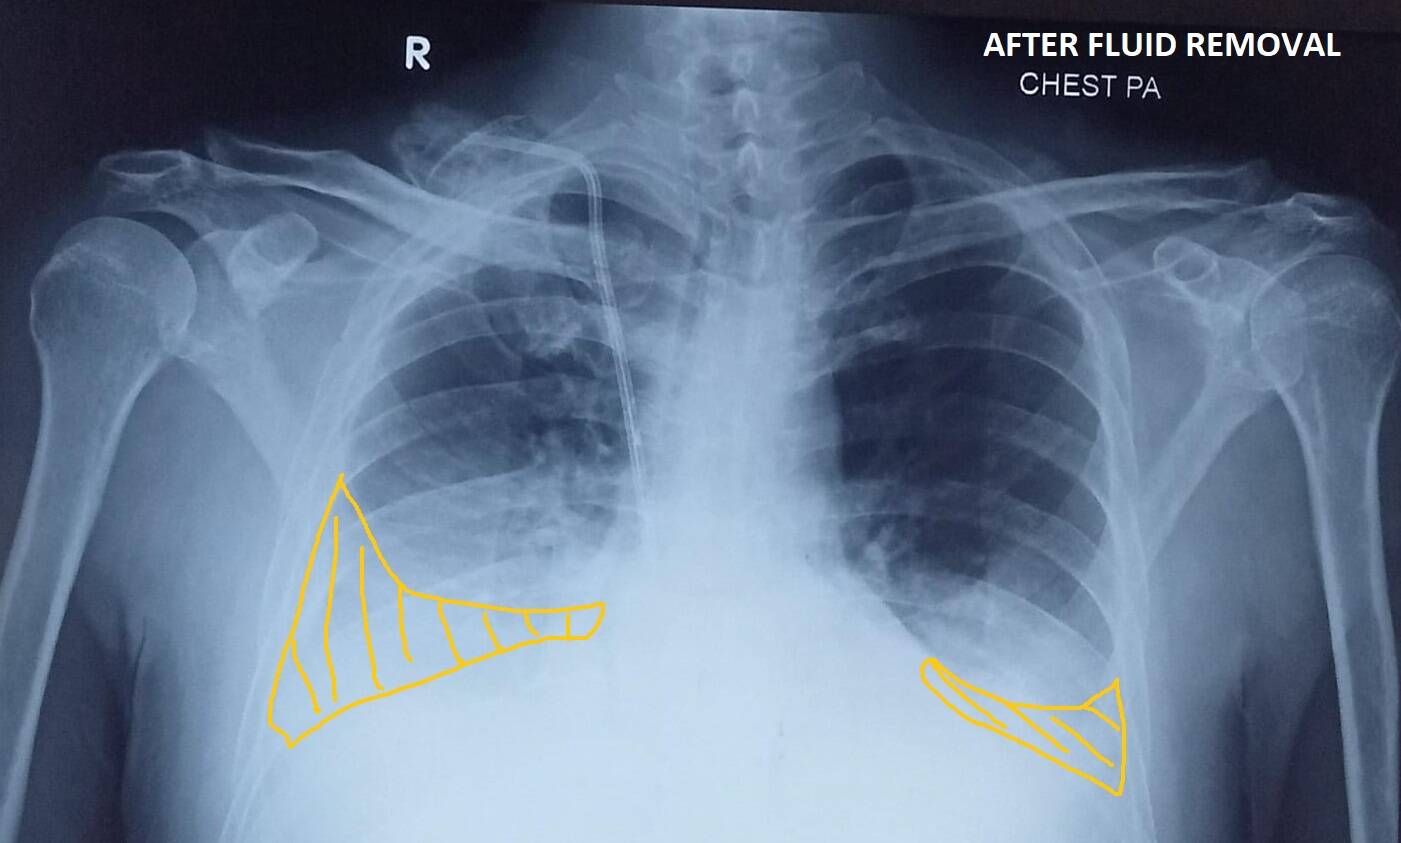

ಇದು ಹೇಗೆ ಆಯ್ತು ಅಂತ ನೀವು ಕೇಳೋದಾದ್ರೆ – ಇವರೊಬ್ಬರು ಕಿಡ್ನಿ ಸಮಸ್ಯೆ ರೋಗಿ. ಈ ವ್ಯಕ್ತಿಯು ಸುಮಾರು ವರ್ಷಗಳಿಂದ ಬಿಪಿ ಮತ್ತು ಶುಗರ್ ಕಾಯಿಲೆಗೆ ಚಿಕಿತ್ಸೆ ಪಡೆಯುತ್ತಿದ್ದರು. ಆದರೆ ಅವರು ವೈದ್ಯರು ನೀಡಿದ ಮಾತ್ರೆಗಳನ್ನು ಪೂರ್ತಿಯಾಗಿ ತೆಗೆದುಕೊಂಡಿಲ್ಲ. ವೈದ್ಯರು ಕೊಟ್ಟಿರುವ ಮಾತ್ರೆಯಲ್ಲಿ ಅರ್ಧ ಡೋಸ್ (Half dose) ತೆಗೆದುಕೊಳ್ಳುವುದು ಅಥವಾ ಕೆಲವೊಮ್ಮೆ ಎರಡು – ಮೂರು ದಿನಕ್ಕೊಮ್ಮೆ (skipping tablets) ಮಾತ್ರೆ ತೆಗೆದುಕೊಳ್ಳುವುದು ಅವರ ರೂಢಿ. ಅವರು ಅಂದುಕೊಂಡಿದ್ದರು ಪ್ರತಿದಿನ ಮಾತ್ರೆ ತಗೊಂಡರೆ ಅದರಿಂದ ಕಿಡ್ನಿ, ಲಿವರ್ ಮತ್ತು ಹೃದಯದ ಸಮಸ್ಯೆ ಬರುತ್ತದೆ. ಮಾತ್ರೆಗಳಿಂದ ಸೈಡ್ ಎಫೆಕ್ಟ್ ಆಗುತ್ತದೆ. ಆದ್ದರಿಂದ ವೈದ್ಯರು ಬರೆದಿದ್ದ ಮಾತ್ರೆಗಿಂತ ಕಡಿಮೆ ಮಾತ್ರೆ ತೆಗೆದುಕೊಂಡರು. ಈ ಕಾರಣದಿಂದಾಗಿ ಅವರ ಬಿಪಿ ಮತ್ತು ಶುಗರ್, ನಿಯಂತ್ರಣದಲ್ಲಿ ಇರಲಿಲ್ಲ. ಅವರು ನನ್ನ ಬಳಿ ಬಂದಾಗ ಕಿಡ್ನಿ ಸಮಸ್ಯೆ ಶುರುವಾಗಿತ್ತು. ಕ್ರಿಯಾಟಿನ್ ಸಮಸ್ಯೆ ಹೆಚ್ಚಿರುವುದರಿಂದಾಗಿ ಅವರಿಗೆ ಡಯಾಲಿಸಿಸ್ (Dialysis / Hemodialysis) ನ ಬಗ್ಗೆ ಹೇಳಿದೆವು, ಅವರು ನಿರಾಕರಿಸಿದರು. ಏನೇ ಚಿಕಿತ್ಸೆ ನೀಡಿದರೂ ಆಗಿರುವ ಹಾನಿ ಸರಿಪಡಿಸಲು ಆಗಲಿಲ್ಲ. ಕಿಡ್ನಿ ಸ್ಪೆಷಲಿಸ್ಟ್ (Nephrology consultation) ಕೂಡ ಭೇಟಿ ಆದರು. ಸಮಸ್ಯೆ ಹೆಚ್ಚುತ್ತಾ ಹೋಯಿತು. ಕ್ರಮೇಣವಾಗಿ ಅವರ ಕ್ರಿಯಾಟೇನಿನ್ ಹೆಚ್ಚಾಗಿ ಅವರ ಆರೋಗ್ಯ ಸ್ಥಿತಿ ಹದಗೆಡುತ್ತಾ ಬಂತು. ಮೂತ್ರದ ಪ್ರಮಾಣ (Reduced urine) ಕಡಿಮೆ ಆಗುತ್ತಾ ದೇಹದಲ್ಲಿ ಯೂರಿಯಾ(Blood Urea), ಕ್ರಿಯಾಟಿನ್ (Serum Creatinine), ಆಸಿಡ್ (Acidosis) ಮತ್ತು ಇತರೆ (Hyperkalemia etc) ತ್ಯಾಜ್ಯ ಪದಾರ್ಥಗಳು ಉಳಿದುಕೊಳ್ಳಲು ಶುರುವಾಯಿತು. ಅವರ ಎದೆಯಲ್ಲಿ ; ಅಂದರೆ ಪುಪ್ಪಸ (Lungs) ಮತ್ತು ಮಾಂಸಖಂಡಗಳ (Chest Wall) ಮಧ್ಯೆ ನೀರು ತುಂಬಿಕೊಳ್ಳಲು ಶುರುವಾಯಿತು. ಇದಕ್ಕೆ ನಾವು ಪ್ಲೂರಲ್ ಎಫ್ಘ್ಯೂಷನ್ (Pleural Effusion) ಎಂದು ಕರೆಯುತ್ತೇವೆ. ಈ ಸಮಸ್ಯೆಯಿಂದ ಅವರು ರಾತ್ರೋರಾತ್ರಿ ಉಸಿರಾಟದ ಸಮಸ್ಯೆಯಾಗಿ ಆಸ್ಪತ್ರೆಗೆ ದಾಖಲಾದರು, ಕೊನೆಗೆ ಡಯಾಲಿಸಿಸ್ ಶುರು ಮಾಡಿದೆವು. ಉಸಿರಾಟದ ತೊಂದರೆ ಹೆಚ್ಚಾದ ಕಾರಣ ಅವರಿಗೆ ಎದೆಯಲ್ಲಿ ಸೂಜಿ ಹಾಕಿ ನೀರನ್ನು ತೆಗೆಯುವ ಸನ್ನಿವೇಶ ಬಂತು (Therapeutic Pleural Tapping).

ಈಥರ ಸಮಸ್ಯೆಗಳ ಲಕ್ಷಣ ಕಂಡುಬಂದಲ್ಲಿ ವೈದ್ಯರು ನಿಮಗೆ ರಕ್ತ ತಪಾಸಣೆ ಮಾಡಿಸುವರು. ಅದರಲ್ಲಿ ಹಿಮೋಗ್ಲೋಬಿನ್, ಲಿವರ್, ಕಿಡ್ನಿ ಪ್ರೊಫೈಲ್ ಮತ್ತು ಆಲ್ಬಮಿನನ್ನು ಪರೀಕ್ಷೆ ಮಾಡುತ್ತಾರೆ. ಇದರ ಜೊತೆಗೆ ಎಕ್ಸರೇ, ಹೊಟ್ಟೆ ಅಲ್ಟ್ರಾ ಸೌಂಡ್ ಸ್ಕ್ಯಾನ್ ಕೂಡ ಸೂಚಿಸುತ್ತಾರೆ. ಹೃದಯದ ಸಮಸ್ಯೆ ಲಕ್ಷಣಗಳು ಇದ್ದಾಗ ಇ.ಸಿ.ಜಿ , ಟಿ.ಎಂ.ಟಿ ಮತ್ತು ಇಕೋ - ಸ್ಕ್ಯಾನ್ ಅವಶ್ಯಕತೆ ಕೂಡ ಬರಬಹುದು.